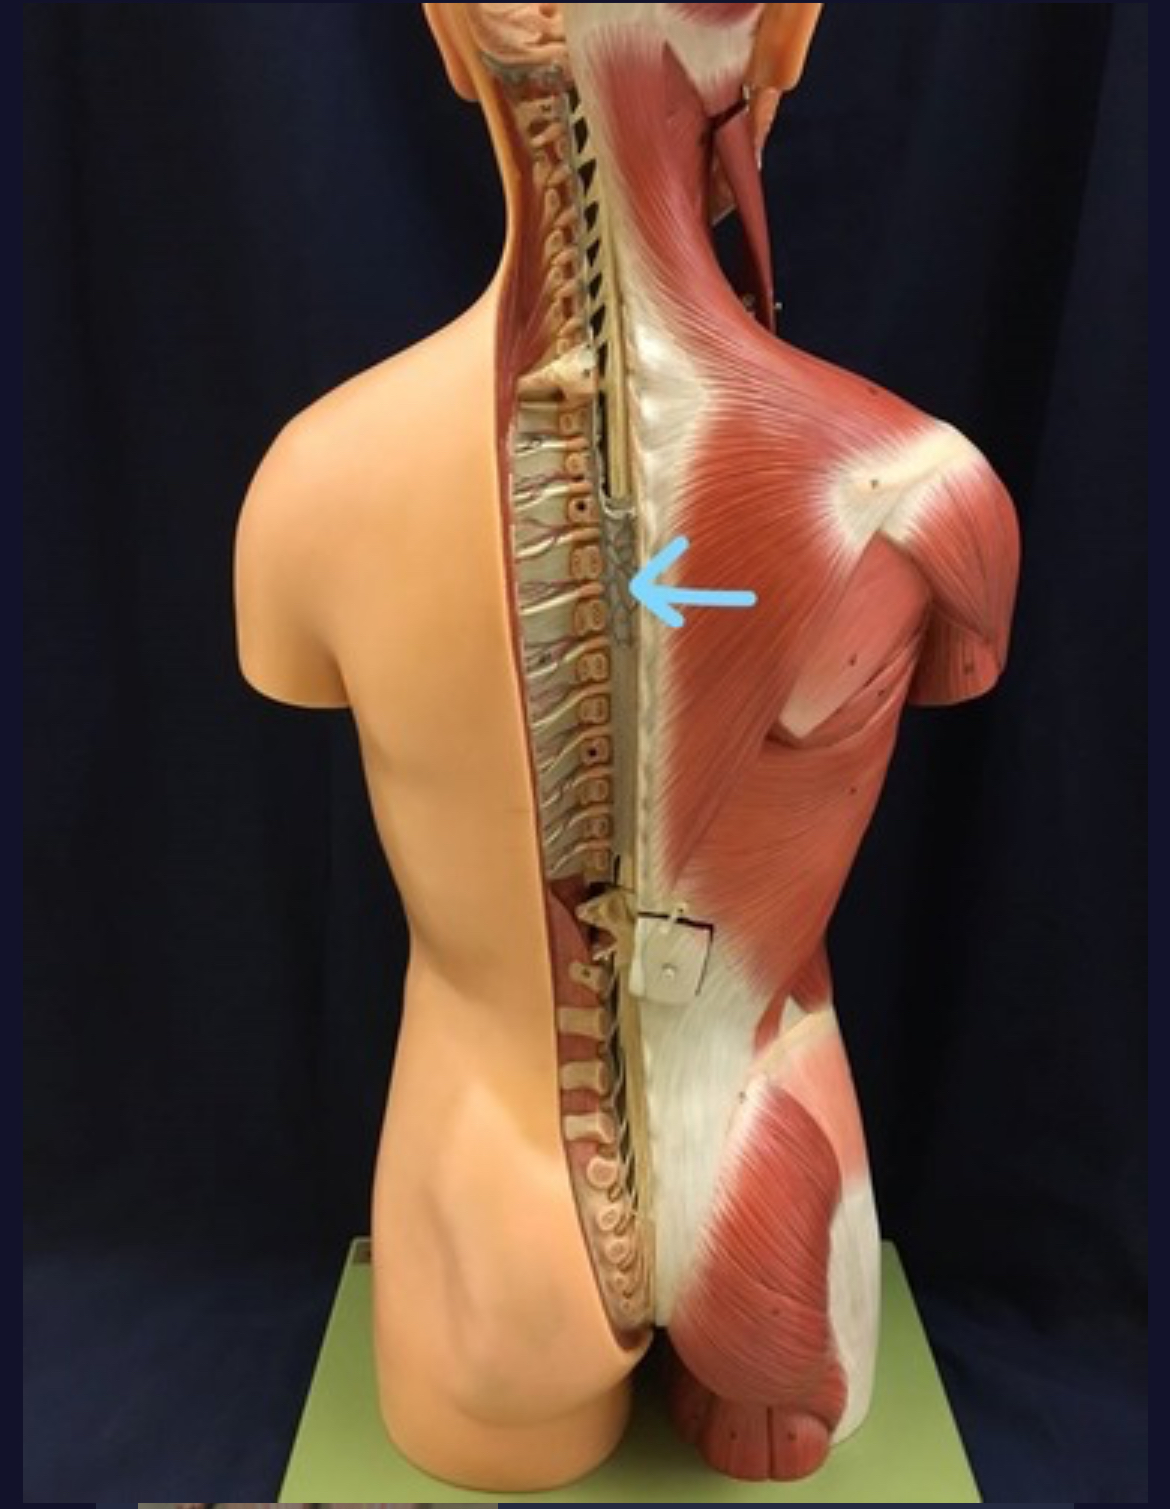

Spinal cord

Dura mater (outermost layer)

White matter of spinal cord

Gray matter of spinal cord

Ventral horns (of gray matter)

Lateral horns

Dorsal horns

Anterior columns of white matter

Lateral columns of white matter

Posterior columns of white matter

Dorsal Ramus

Ventral ramus